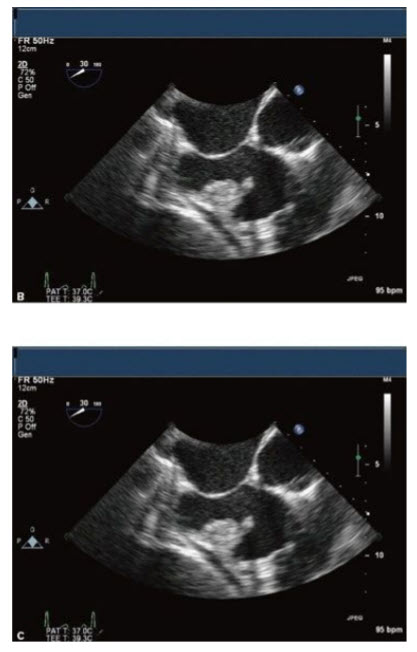

The images in Figures below A–C are from a 43-year-old s/p carpentier edwards aortic valve replacement (CE AVR) with fevers and night sweats.

These images demonstrate all of the following except:

Aortic insufficiency (AI). Although all of the answers are possible complications of infective endocarditis, the images displayed in Figures in question do not show any significant AI. Figure A in question shows the short axis of a bioprosthetic AV with a paravalvular abscess with vegetations. It also shows the valve during systole which although it is open, the opening is restricted suggestive of AS which is confirmed by the peak AV gradient of 92.6 mmHg shown in Figure B in question. Figure C in question shows the long-axis TEE view of the AV with a small fistula into the LA (seen at the top of the image).